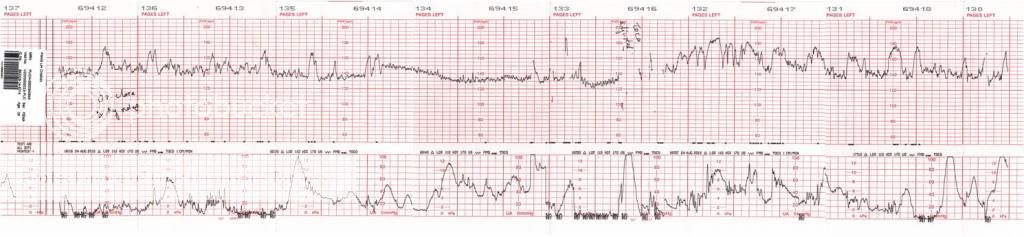

抵达医院后,我们就直接到急诊室去报到。我告诉那里的护士说我有阵痛,可是没来红或破水。她吩咐我坐在一张轮椅后,就由一个男护士推我上一楼的产房去。到了那里,值班的护士就叫我躺在床上,然后她拿了一个探测器开始找宫缩的地方。找到后,她就把它绑在我的肚子上。接着她拿了另一个探测器找小贝比的心跳,同样的,找到后,她又把它绑在我的肚子上。下面的图表就是由那两个探测器测量出来的,上面那一部分显示小贝比的心跳,中间有断断续续的横线是小贝比的胎动,而下面那一部分显示我的宫缩程度。就在我们赞叹着这仪器很先进时,那护士告诉我们说外面已经有更先进的,还有荧幕显示呢。现在这个也不便宜,一台要价十千,所以院方没打算换。

我有问那助产护士可以做些什么来帮助子宫颈打开,呜呜,她说没有,一切顺其自然。然后她也有说如果这几天我有破水的话,不管那羊胎水是透明的还是带有黑或墨绿色,都一定要到医院去。如果那羊胎水是黑或墨绿色的话,那表示宝宝在里面便便了,是很危险的。内检后,通常会有来红一点点,只要不是鲜血,那就ok。还有,真的阵痛其实是整个腹部都会感觉痛的,不是像我现在只有中间和下面痛而已。哦,知道了。总之只要没来红或破水,有阵痛的话,我能忍就不到医院去好了。她们打电话给Dr Ng确认后,就说我不需留院,可以回家。如果我到9月1号都还没生,就照着预约的时间去见Dr Ng。由于有一段时间小贝比的心跳不是很美,一直保持在低迷状态(图表的中间那一段),那助产护士就留我在那里观察多一会儿。她说可能是小贝比睡着了,所以才会那样。她调整了我的姿势并且摇我的肚子弄醒小贝比后,小贝比一开始动,心跳就上升了。谨慎的确定一切没问题后,她才让我们回家。虽然虚惊一场,白白浪费了RM70,但是这次让我见识到Columbia Asia Puchong接生队专业的服务精神及态度,我可以很肯定我没选错医院而安心在那里分娩了。